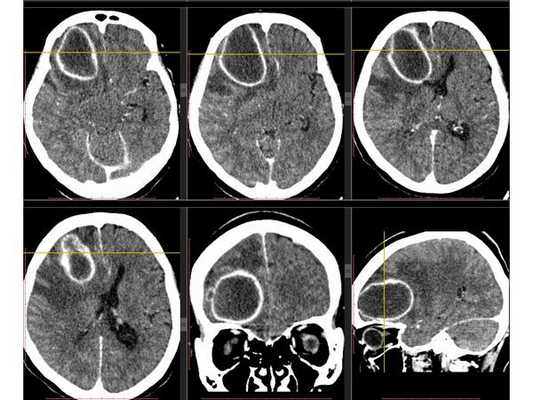

Рентгенография лёгких: без патологии. УЗИ органов брюшной полости: выявлены хронический холецистит, хронический панкреатит, диффузные изменения печени и поджелудочной железы. ЭКГ: в норме. На КТ головного мозга визуализировалось объёмное образование в правой лобной доли. Это вызвало подозрение на абсцесс, но отсутствие уровня жидкости, лихорадки и менингеального синдрома у пациентки в большей степени склонило клиническую мысль в сторону онкологического поражения. В связи с этим пациентку госпитализировали в отделении неврологии. Однако при осмотре онкологом и гинекологом данных, которые бы подтверждали наличие онкологии головного мозга, обнаружено не было. В качестве дообследования проведена КТ головного мозга с контрастным усилением. Она выявила объёмное образование в правой лобной доли с чётко очерченной капсулой. Рядом с образованием располагался отёк, срединные структуры были смещены влево примерно на 5 мм.

3D-реконструкция объёмного образования правой лобной доли головного мозга, выполненная на основании сканов КТ с контрастным усилением

Инкапсулированный абсцесс мозга на КТ имеет вид округлого объемного образования с четкими ровными контурами повышенной плотности (фиброзная капсула). В центре капсулы зона пониженной плотности (гной), по периферии видна зона отека. Введенное контрастное вещество накапливается в виде кольца (по контуру фиброзной капсулы) с небольшой прилежащей зоной глиоза.

На повторной КТ (через 30-40 минут) контрастное вещество не определяется. При исследовании результатов компьютерной томографии следует учесть, что противовоспалительные препараты (глюкокортикостероиды, салицилаты) в значительной степени влияют на скопление контраста в энцефалитическом очаге.